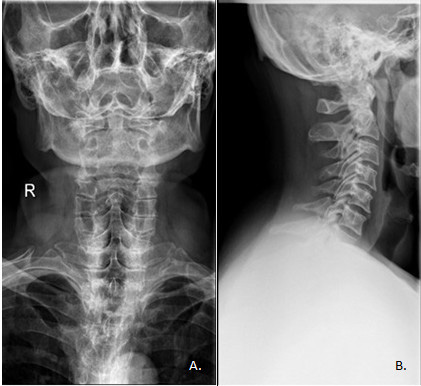

Materiały i metody: Analizie retrospektywnej poddano 150 kolejnych zdjęć rentgenowskich kręgosłupa w odcinku szyjnym, wykonanych w dwóch projekcjach: przednio-tylnej (AP) i bocznej (LAT). Przeprowadzono pomiar długości i szerokości radiogramów oraz obliczono pole powierzchni. Przyjęto wartość referencyjną dla obu projekcji 18 x 24 cm (pole 432 cm2). Radiogramy zostały wykonane w okresie 19.05.2015-12.10.2015 w Zakładzie Radiologii Uniwersyteckiego Szpitala Klinicznego w Białymstoku. Analizę statystyczną przeprowadzono przy użyciu programów MS Excel 2010 oraz Statistica 12.

Wyniki: Najczęściej radiogramy wykonano kobietom (n = 104; 69,33%) w wieku 24-80 lat (Me = 57). Średnia wartość pola kolimacji zdjęcia RTG w projekcji przednio-tylnej wyniosła 284,54 cm2, SD = 3 2,19 c m. N ajwiększe o dnotowane p ole p owierzchni r entgenogramu AP wyniosło 414,03 cm2, natomiast najmniejsze 235,83 cm2. Średnia powierzchnia radiogramu w projekcji bocznej wyniosła 349,54 cm2, SD = 94,54 cm, a wartość maksymalna 645,05 cm2 i minimalna 231,12 cm2. Pole kolimacji radiogramu LAT zostało przekroczone w 19,33% przypadków. Najczęściej (n = 51; 34%) długość radiogramu LAT nie spełniała założonego kryterium. W przypadku zdjęć RTG AP nie odnotowano przekroczenia wartości referencyjnej pola wiązki promieniowania.

Wnioski: Co piąte zdjęcie w projekcji bocznej miało wartość pola kolimacji większą od wartości referencyjnej. Zwiększenie pola wiązki promieniowania może być skutkiem obawy technika wykonującego ekspozycję przed nieobjęciem polem kolimacji całego obszaru, który powinien być widoczny na poprawnie wykonanym radiogramie.